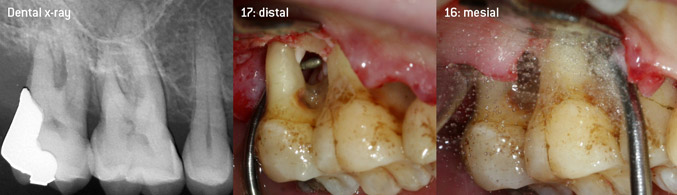

Come pionieri dello sviluppo della nuova punta per ablatori 3AP diamantata, i due dentisti hanno riconosciuto la necessità di migliorare le restrizioni di manipolazione delle punte diamantate disponibili in commercio, specialmente durante il trattamento della forcazione e lavorando su tasche intraossee strette. Tutto ciò deve essere fattibile sia per procedure non chirurgiche (figura 2) sia per procedure chirurgiche (figura 3).

(Foto (figure 2-4): © Dott. Christian Graetz)

L'idea era di sviluppare una punta applicabile universale al fine di evitare le sostituzioni della punta, per cui era richiesto parecchio tempo. Inoltre, si doveva facilitare l'utilizzo delle nuove punte in tasche intraossee strette dalla parte distale e all'entrata della forcazione distale dei molari mascellari, per consentire così un utilizzo più efficace degli strumenti. Ciò è stato possibile adottando una curva dello strumento con un diametro più ampio (figura 1), un vantaggio enorme in particolare per il debridement chiuso sui denti con perdita avanzata degli attacchi e dove entra in gioco la forcazione (figura 4).